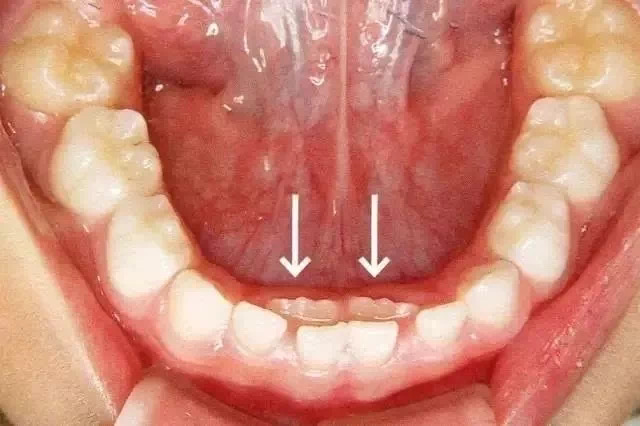

幼儿园高年级和小学低年级的父母们,这个情况是不是经常碰到?为什么会发生这种事情呢?孩子这是乳牙还没脱落,新牙就长出来了,表现为”双排牙“现象。这种情况就是我们所说的“乳牙滞留”。

箭头所指为恒牙